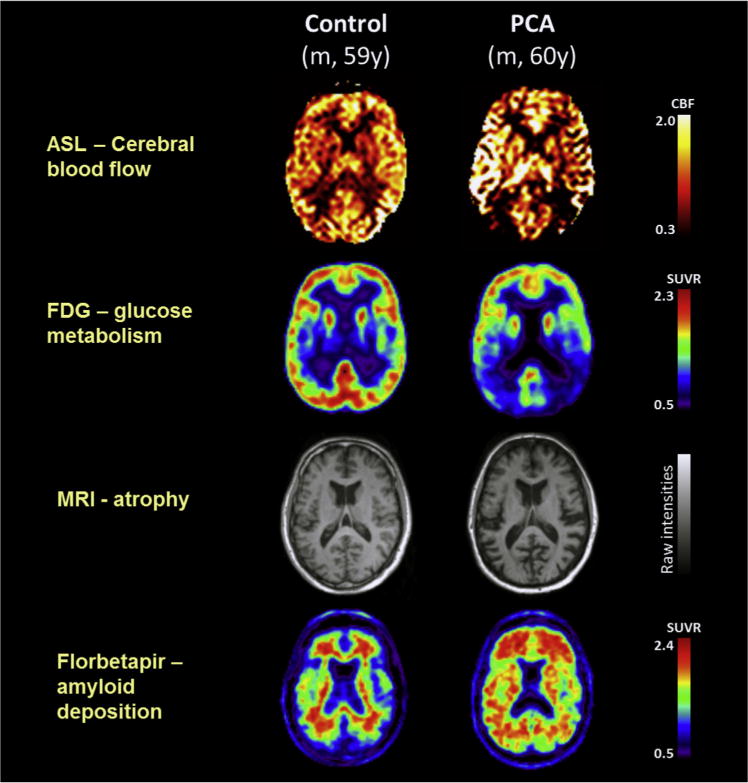

| Predominant occipito-parietal or occipito-temporal atrophy/hypometabolism/hypoperfusion on MRI/FDG-PET/SPECT |

The neuroimaging features of PCA are intentionally broad to reflect the loose anatomical description of “posterior cortical atrophy,” with the working group regarding evidence of focal structural (e.g., atrophy on magnetic resonance imaging) or functional (e.g., hypometabolism on 18F-labeled fluorodeoxyglucose positron emission tomography or single-photon emission computed tomography) abnormality in the occipital, parietal, and/or occipito-temporo-parietal cortices as supportive of the clinico-radiological syndrome. The inclusion of neuroimaging evidence of posterior cortical atrophy or dysfunction as an optional, supportive feature rather than obligatory component of the syndrome-level description is consistent with previous criteria. This issue generated considerable debate, but maintaining the optional status was justified on both clinical (e.g., variable extent of atrophy at presentation) and practical grounds (e.g., accessibility of neuroimaging facilities; not wishing to exclude patients unable to undergo M.R. investigation from all PCA-related research). Where for practical reasons neuroimaging evidence cannot be obtained, research studies should specify the evidence used to support the classification of PCA. Another issue is that individuals with the visual variant of Creutzfeldt–Jakob disease typically decline rapidly such that obvious focal atrophy is not easily demonstrated [ref. 25–ref. 27]. We debated the utility of classifying such individuals within the PCA framework, which may only be appropriate for prion disease patients with an insidious (rather than rapid) progression ([ref. 16], subject [ref. 21,ref. 28]). It should also be noted that evidence provided by more recently established molecular imaging techniques is incorporated together with other in vivo biomarkers in the disease-level description (see classification level 3).